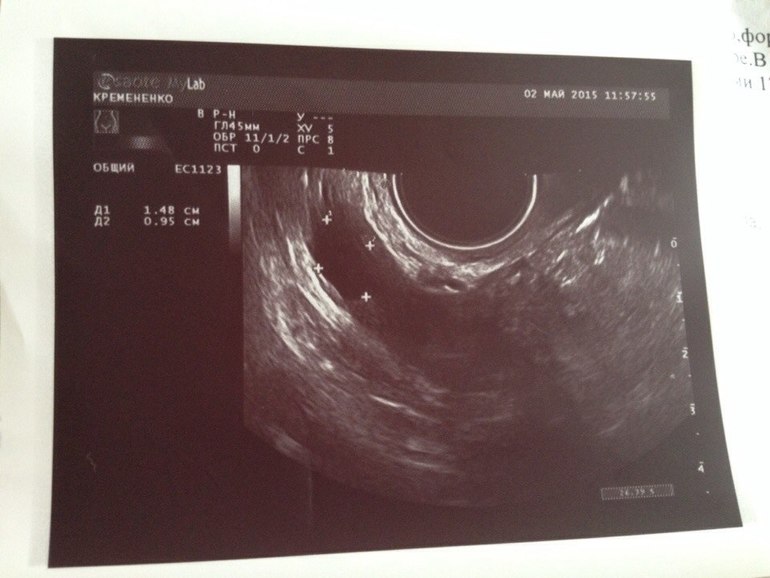

Сегодня 9 ДЦ. Сходила на фолликулометрию, результат которой смущает. Фото УЗИ ниже Есть один фолик 17 х 2 мм в ЛЯ - с ним ясно, что это не ДФ, а остатки с прошлых циклов. Но в ПЯ есть фолик 15 х 9 мм и на счет него врач тоже сказала, что он не похож на ДФ, т.к. овальной формы...

Могут ли нормальные ДФ быть не круглой, а овальной формы?

И могла ли врач просто ошибиться и не совсем верно измерить? Фото прикрепляю.

Я конечно могу ошибаться, но когда смотрю в экран на УЗИ, то фоллики там всегда не круглые.. А почему вы решили, что в ЛЯ не доминант, а с прошлого цикла? разве за М желтое тело не рассасывается? По мне так у вас два доминантных сейчас в ЛЯ и ПЯ. Эндометрий тонковат, но трехслойный это хорошо, овуляции на 11-12-13 дц должна быть.

Про то, что в ЛЯ не доминантный фолликул мне сказала врач, которая делала узи. Сказала, что он прям слишком вытянут - 17 на 2 мм. Вы правы- ЖТ с прошлого цикла ушло бы. Может это какая-то старая киста.. Сложно сказать, т.к прошлые два цикла особо не наблюдалась. А вот в ПЯ есть надежда, мне кажется. Правда врач тоже сомневается на этот счет))) но могла неточно измерять. А эндик предсказуемо мал-два дня только как М закончились, а цикл обычно скачет. Меня смутило , что она сказала про овальную форму, что вроде как ДФ обычно круглые ... ))) Спасибо Вам за отклик! На 14 ДЦ схожу проверю еще разок.)))